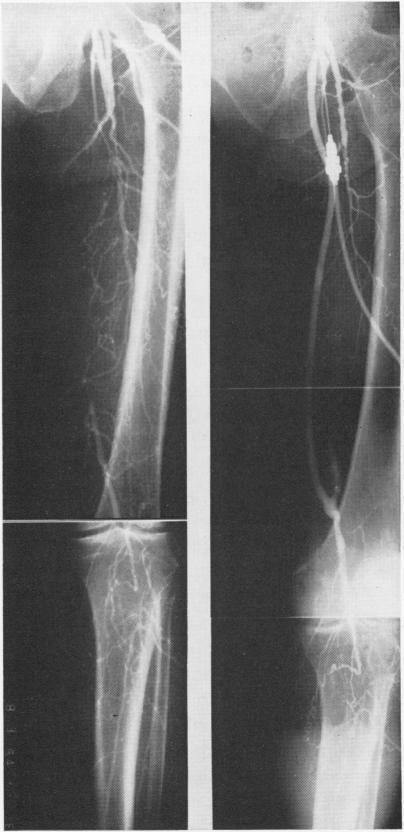

Autogenous venous bypass grafts five years later.

Ann Surg. 1971 Sep;174(3):346-56. doi: 10.1097/00000658-197109000-00003.